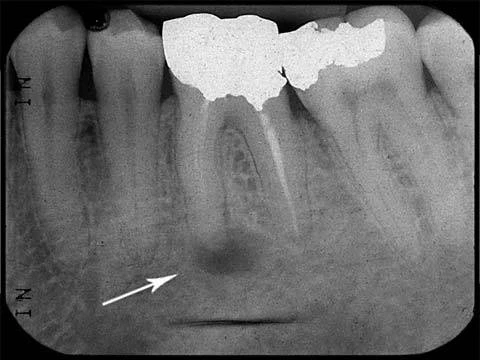

Tủy hoại tử

Tuỷ răng hoại tử có thể bán phần hoặc toàn bộ, có thể không liên quan đến tất cả các ống tuỷ ở răng nhiều chân. Vì lý do này, răng có thể có những triệu chứng dễ nhầm lẫn chẳng hạn như thử nghiệm tuỷ ở một chân răng có thể không đáp ứng nhưng chân răng khác lại đáp ứng. Răng cũng có thể biểu hiện những triệu chứng của viêm tuỷ không có khả năng hồi phục có triệu chứng. Sau khi tuỷ răng hoại tử, vi khuẩn có thể phát triển bên trong ống tuỷ. Khi quá trình nhiễm khuẩn (hoặc độc tố vi khuẩn từ nhiễm trùng này) lan rộng đến khoảng dây chằng quanh chóp, răng có thể biểu hiện triệu chứng khi ấn/gõ hoặc đau tự phát. Trên X-quang có thể thấy những thay đổi như giãn dây chằng nha chu cho đến thấu quang quanh chóp. Răng có thể nhạy cảm với nhiệt độ nóng và thường giảm đau khi đặt nhiệt lạnh. Như đã được thảo luận trước đây, điều này có thể giúp xác định vị trí răng có tuỷ hoại tử khi cơn đau là lan toả hoặc xuất chiếu.